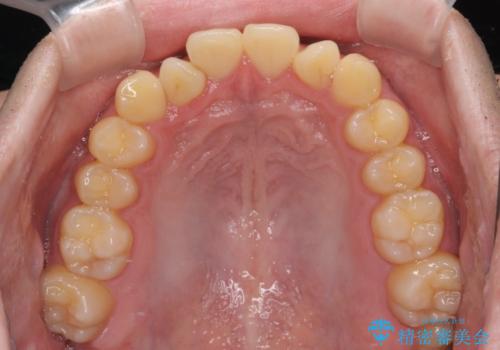

- 上下前歯の捻れやデコボコを気にして来院された患者様です。

マウスピース矯正でもワイヤー矯正でも対応可能でしたが、極力楽をして治したいとのことでワイヤー装置にて治療をおこなうこととしました。

口元はそれほど突出しておらず、患者様自身も気にしていらっしゃいませんでしたが、前歯の捻れやデコボコを解消すると、前方に拡大され、治療後に出っ歯仕上がりとなるリスクがあったため、補助装置により上顎臼歯を後方移動していくこととしました。

昼休みを活用して通院してくださり、1年半であっという間に終えることができました。